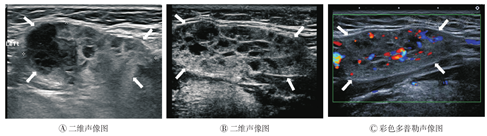

弥漫性结节样改变,共11例12灶(54.5%)。病侧腺体长径约2.7~4.6 cm,平均(3.7±0.56)cm,厚径约0.7~2.5 cm,平均(1.9±0.49)cm。8灶病侧腺体局部隆起,4灶病侧腺体形态无明显变化;均与周围组织分界清楚。颌下腺内部呈网格状或蜂窝状,未显示正常腺体回声。具体表现为腺体回声增强、增粗、不均匀,内见弥漫、散在、大小不一的结节样低回声区,低回声周围显示条状强回声(图3A、图3B),整个腺体血流丰富(图3C)。病变以腺体的边缘、浅侧为著。